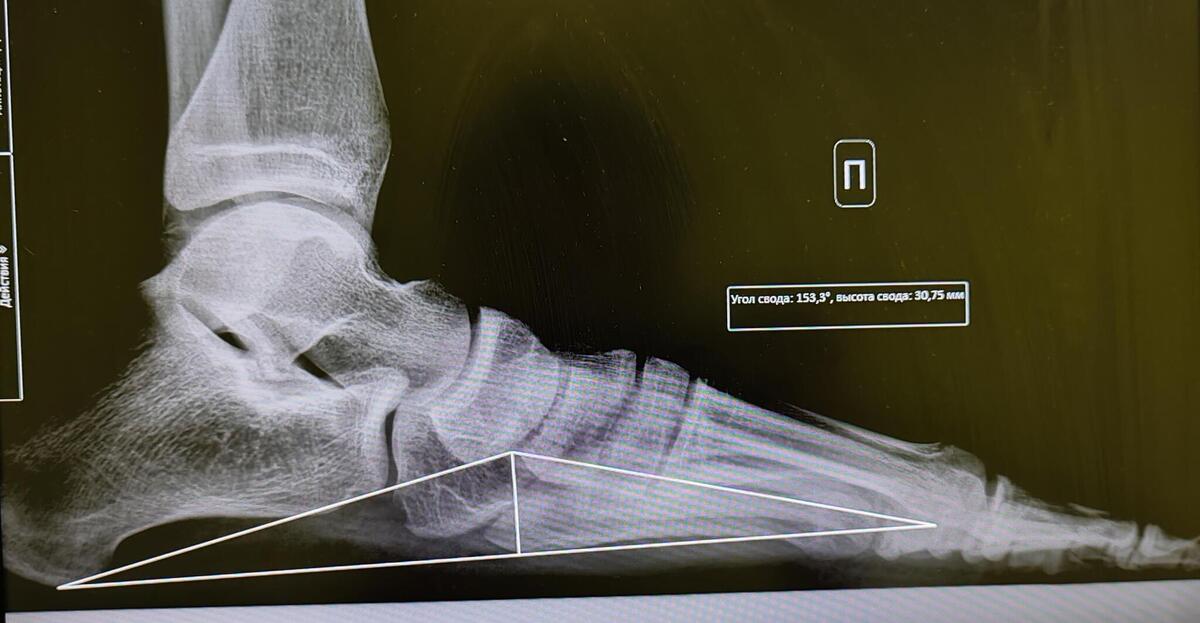

Плоскостопие 3 Фото

Плоскостопие 3 Фото 108 фото